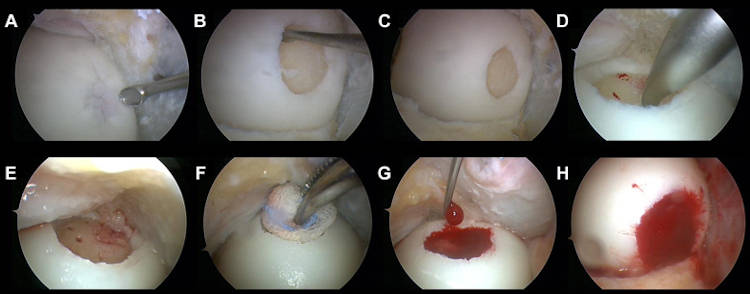

Τεχνική των μικροκαταγμάτων όπου με ειδικό εργαλείο δημιουργούνται μικρές οπές στο σημείο της βλάβης στο υποχόνδριο, ώστε να απελευθερώνεται αίμα πλούσιο σε αναγεννητικούς παράγοντες στο σημείο της βλάβης με αποτέλεσμα προοδευτικά να σχηματίζεται χόνδρος ινώδης στην περιοχή. Ο συγκεκριμένος χόνδρος δεν έχει τις ιδιότητες του υαλοειδούς χόνδρου είναι λιγότερο εύκαμπτος και ελαστικός. Η τεχνική δείνει να είναι αρκετά αποτελεσματική σε βλάβες χόνδρου μέχρι 2 εκατοστά και καλή ποιότητα υποχόνδριου ιστού.

Τεχνική καθήλωσης σε αποκόλληση χόνδρου με ειδικές καρφίδες σε περιπτώσεις διαχωριστικής οστεοχονδρίτιδας.

Τεχνική μεταμόσχευσης αυτόλογων οστεοχόνδρινων κυλίνδρων για βλάβες μέχρι 4 εκατοστά (OATS-mosaicplastic), λαμβάνονται κυλινδρικά οστεοχόνδρινα τμήματα από μη φορτιζόμενες περιοχές της άρθρωσης και τοποθετούνται στη βλάβη με αποτέλεσμα να έχουμε υαλοειδή χόνδρο.

Τον τελευταίο χρόνο, η ομάδα της Β' Ορθοπαιδικής Κλινικής του Ιασώ Θεσσαλίας χρησιμοποιεί την τεχνική Graftnet με εντυπωσιακά αποτελέσματα, όπου στον ίδιο χρόνο συλλέγει υγιή χόνδρο από μη φορτιζόμενη επιφάνεια, τον δυναμοποιεί και ενεργοποιεί ανακατεύοντας τον με αυτόλογους αυξητικούς παράγοντες και τον επανατοποθετεί στη περιοχή της βλάβης όπου θα αναπτυχθεί νέος αρθρικός χόνδρος.